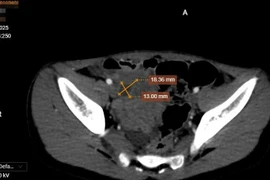

Vừa qua, các bác sĩ khoa Phụ sản Bệnh viện Quốc tế City đã thực hiện thành công ca mổ bắt con khẩn cấp cho sản phụ L.T.T. (TP HCM), mang thai 31 tuần trong tình trạng tiền sản giật nặng, suy thận cấp tiến diễn và suy thai cấp - một trong những biến chứng sản khoa nguy hiểm nhất.

Bệnh nhân nhập viện với huyết áp 180/120 mmHg, protein niệu 3+, phù toàn thân và men gan tăng. Mặc dù được điều trị nội khoa tích cực, nhưng tình trạng diễn tiến xấu: suy thận cấp, toan hóa máu, tăng kali máu. Việc monitoring liên tục ghi nhận tim thai giảm dao động, dấu hiệu suy thai cấp, có thể chuyển sang nguy kịch bất cứ lúc nào.

Nhận định tình huống nguy hiểm, TS.BS Tạ Thị Thanh Thủy - Trưởng khoa Phụ sản đã chỉ đạo kích hoạt mổ khẩn, phối hợp chặt chẽ cùng ê-kíp Gây mê Hồi sức và Nhi sơ sinh.

Ca phẫu thuật diễn ra trong bối cảnh cả mẹ và con đều suy nặng. Bé gái 1.100g được đưa ra khỏi bụng mẹ trong tình trạng không thở, không khóc, mềm nhũn. Ê-kíp Nhi sơ sinh đã hồi sức khẩn cấp, sau khoảng 1 phút, bé có nhịp thở trở lại, được hỗ trợ CPAP và chuyển về NICU.

Tại đơn vị hồi sức sơ sinh, bé được bơm surfactant hỗ trợ phổi, nuôi dưỡng tĩnh mạch toàn phần qua catheter rốn và theo dõi nhiễm trùng, xét nghiệm và hình ảnh học liên tục.

Bệnh viện cho biết hiện bé đã tự thở, tiêu sữa tốt và tăng cân đều.

Về phía sản phụ, sau mổ được lọc máu liên tục và điều trị tại ICU. Huyết áp được kiểm soát, chức năng thận cải thiện, sức khỏe tiến triển tích cực và đã ra khỏi hồi sức.